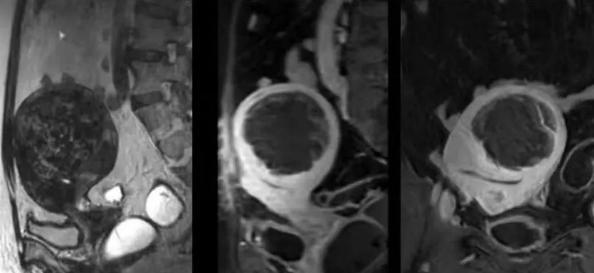

陳寶瑩主任首先給祝女士進(jìn)行了詳細(xì)的盆腔磁共振評估,發(fā)現(xiàn)子宮肌瘤比較大,直徑七公分,類型和位置都適合做磁波刀治療。陳寶瑩主任立即為她制定了個性化治療方案,并為她完成幾項術(shù)前檢查。

治療當(dāng)天,為緩解祝女士的緊張心情,陳寶瑩主任和她進(jìn)行了充分溝通。術(shù)前準(zhǔn)備就緒后,治療正式開始了。治療過程中,患者全程清醒,可以及時反饋治療感受。醫(yī)生也即時調(diào)整,確保整個治療安全有效,兩小時后治療順利結(jié)束,患者體驗度好。即時評估發(fā)現(xiàn)7公分的子宮肌瘤被消融掉80%,達(dá)到了預(yù)期目標(biāo)。祝女士觀察一個小時后,沒有什么不舒服即回家了。